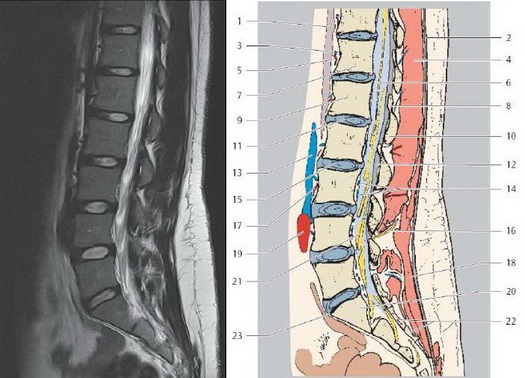

МРТ грудного отдела позвоночника (сагиттальная проекция, Т1 ВИ)

Секционная анатомия позвоночника

Цветные обозначения позвоночного столба.

МРТ позвоночника

1. Выйная связка

2. Зуб второго шейного позвонка

3. Выступающий позвонок С 7

4. Тело грудного позвонка Т1

5. Позвоночный канал

6. Грудной отдел спинного мозга

7. Межпозвоночный диск

8. Надостистые связки

9. Подостистые связки

10. Тело поясничного позвонка L1

11. Мозговой конус

12. Конский хвост

13. Остистый отросток

14. Текальная сумка

15. Крестец (S1)

16. Мыс крестца

17. Копчик